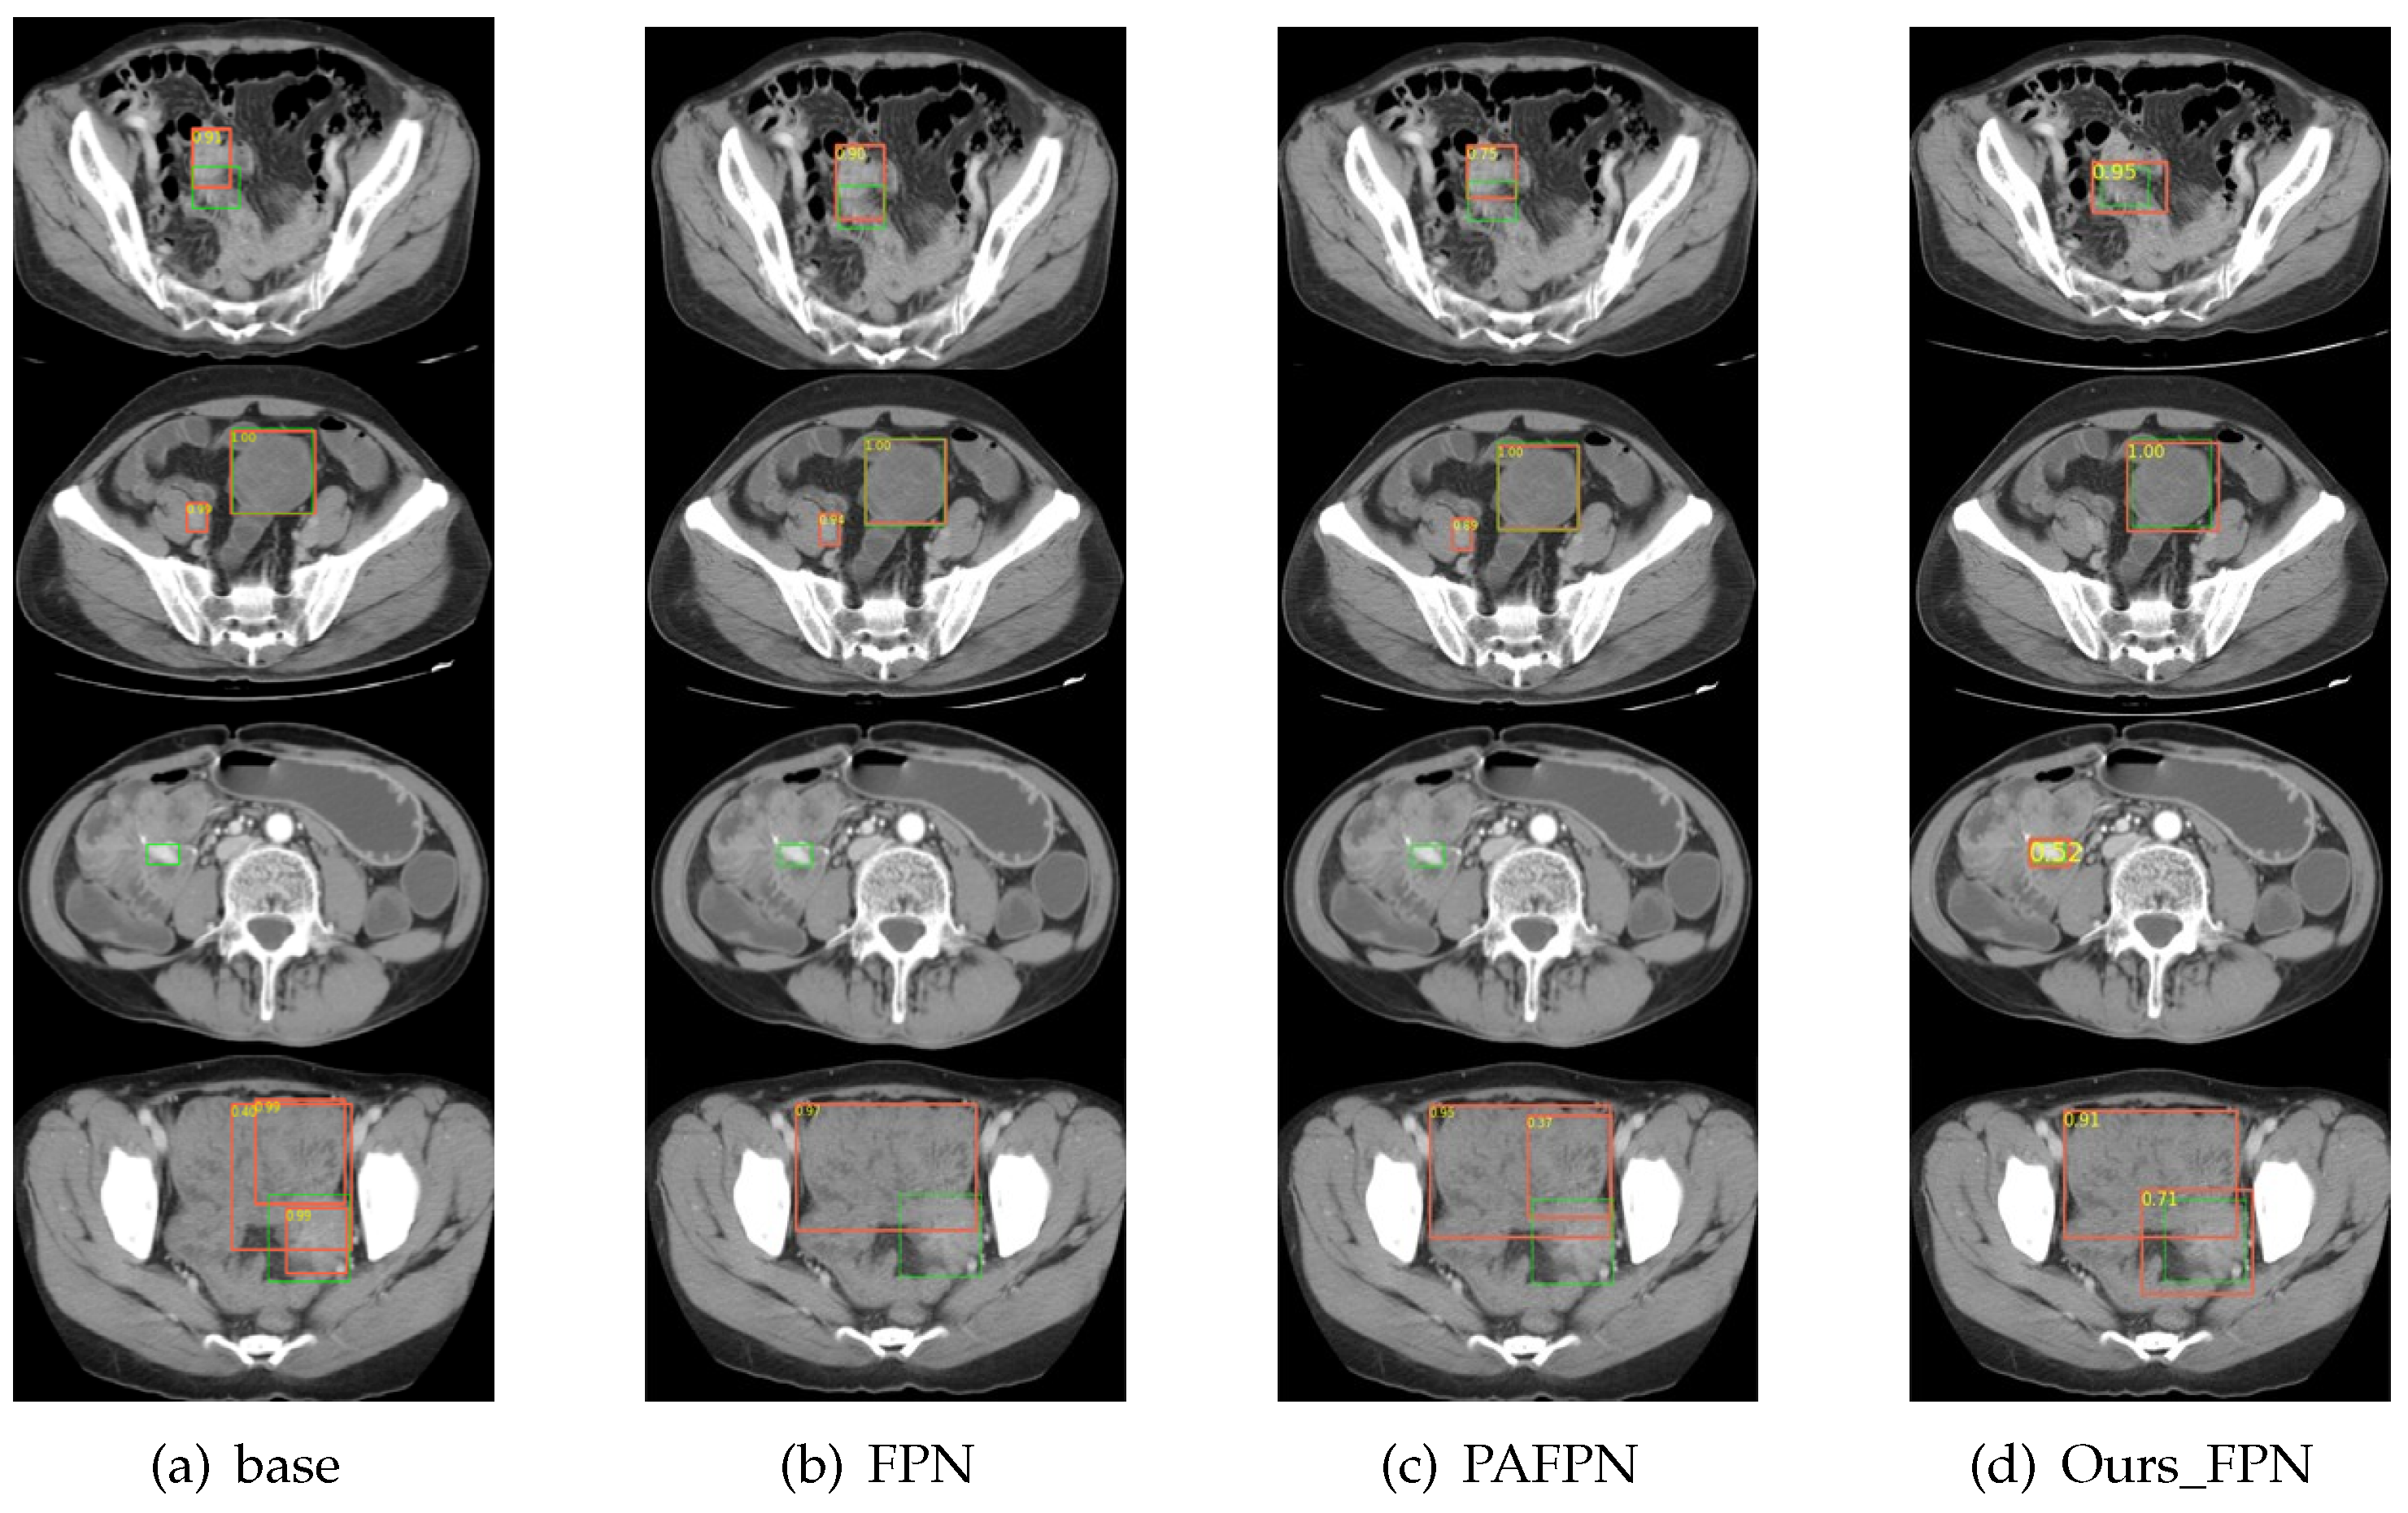

In this section, we describe the series of comparative experiments conducted to prove the superiority of the Improved Faster R-CNN and the proposed self-training method. As shown in Table 7 and Figure 6, the Improved Faster R-CNN outperformed the other mainstream object detection algorithms, including the one-stage object detector, two-stage object detector, and anchor-free object detector, which demonstrates that our network has superiority by virtue of the multiscale module and the FEM.

Figure 6. Visual comparison of the different object detection algorithms including (a) Faster R-CNN, (b) Mask R-CNN, (c) Cascade R-CNN, (d) YOLOv3, (e) RetinaNet, (f) FCOS, and (g) Improved Faster R-CNN. The orange bounding box in the figure represents the predicted box, and the green bounding box represents the actual labeled box.